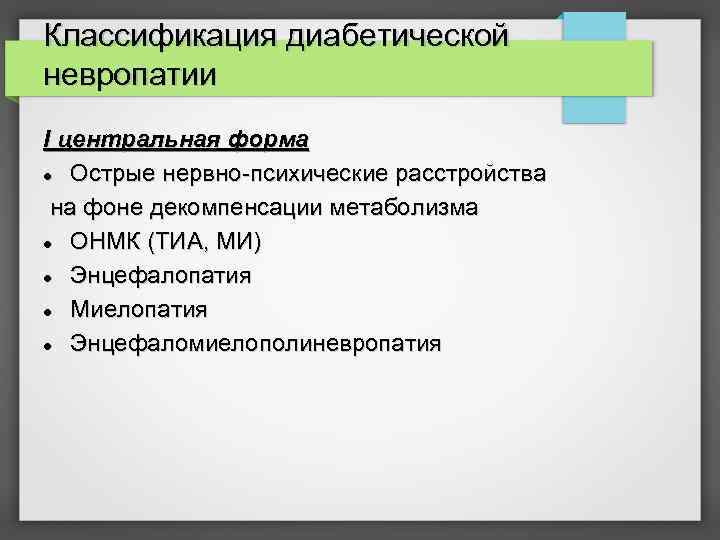

Классификация диабетической невропатии I центральная форма Острые нервно-психические расстройства на фоне декомпенсации метаболизма ОНМК (ТИА, МИ) Энцефалопатия Миелопатия Энцефаломиелополиневропатия